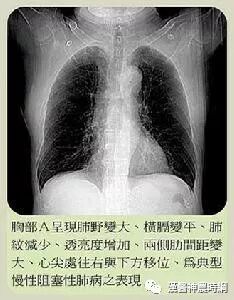

慢性阻塞性肺炎(COPD)

我国是个慢阻肺大国,40岁以上人群中有14%的人患有慢阻肺。得了慢阻肺,就是长期的呼吸困难、咳嗽、咳痰,肺功能会受到影响和损坏。

慢阻肺发生受到吸入颗粒总量的影响,所以吸烟是第一影响因素,其次是空气污染等问题。但是,体育锻炼也能影响慢阻肺的发生,锻炼不足,慢阻肺发生风险提高89%。